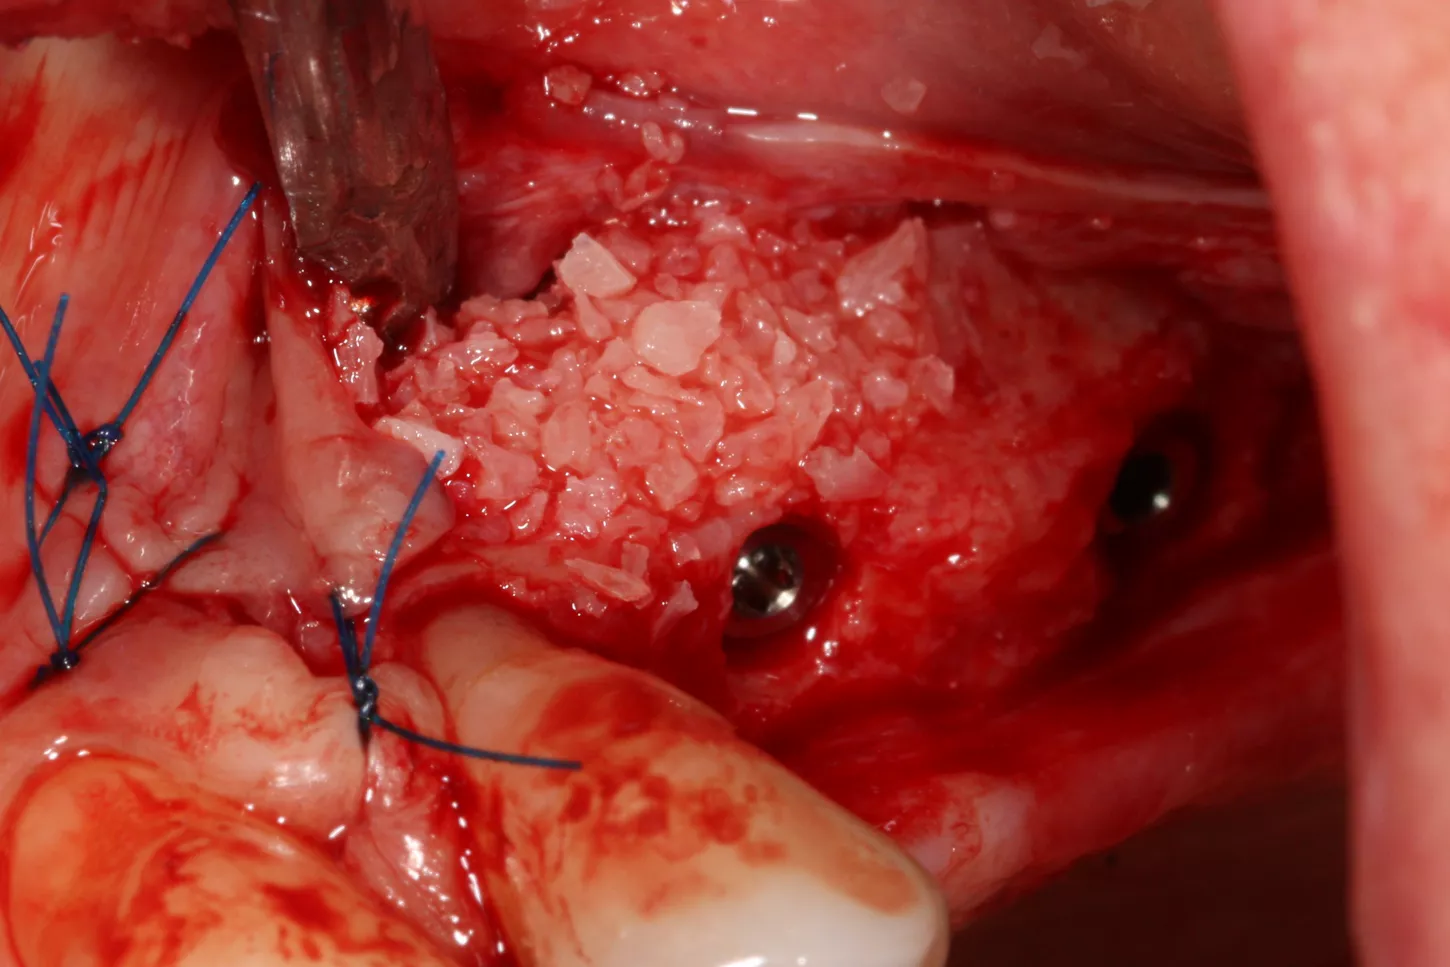

8. The sinus was elevated with cortical/cancellous allograft of a particle size of 0.5 mm and volume of 1.5 cc.

14. Graft material added to the vestibular aspect of 25 to offset the bone loss and ensure long-term implant survival.